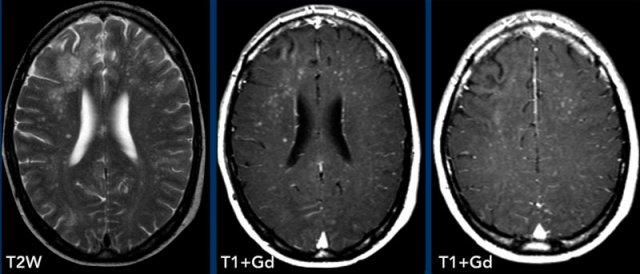

Các hình ảnh này thuộc về một bệnh nhân HIV đã bắt đầu điều trị HAART 2 tuần trước và nhập viện vì rối loạn hành vi.

Hình ảnh

Trên chuỗi xung T2W, chất trắng thùy trán phải tăng tín hiệu.

Lưu ý hình ảnh ngấm thuốc dạng chấm trên các lát cắt axial, thực chất là dạng tuyến tính trên các lát cắt coronal hoặc sagittal (không hiển thị).

Đây là kiểu ngấm thuốc quanh mạch máu và kết hợp với tiền sử bệnh, chẩn đoán là PML-IRIS.